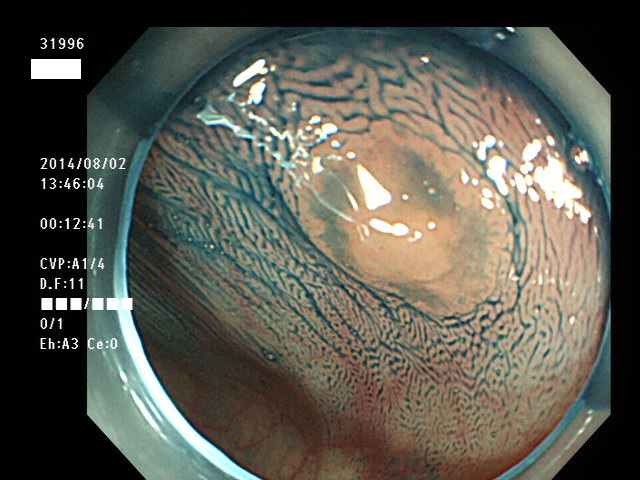

上記100名より抽出した平坦・陥凹型腺腫(=癌化の危険が高いが見落としやすい病変)の内視鏡写真